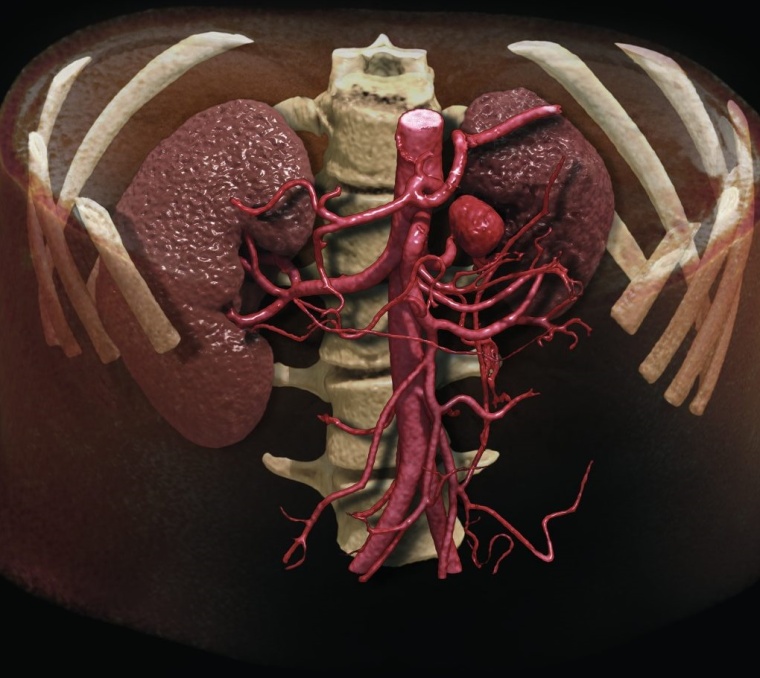

Dank künstlicher Intelligenz und neuer 3D-Rendering-Technik ist ein fotorealistischer Blick auf die Anatomie möglich.

Global Illumination von Canon Medical ist eine neue innovative 3D-Rendering-Technik, die einen präzisen und fotorealistischen Blick auf die Anatomie ermöglicht. Mittels dieses hochqualitativen alternativen Blickeindruckes wird die Diskussion unter Ärzten, mit Patienten und weiteren Gesprächspartnern (z. B. der Gerichtsmedizin) einfacher und effizienter, da die Befunde plastischer erscheinen und leichter verständlich sind. Die einfach zu bedienende Software erzeugt fotorealistische Bilder und Videos, sie wurde kürzlich erstmals der Weltöffentlichkeit im Detail vorgestellt und ist für die Vitrea-Software von Canon Medical erhältlich.

Das ultrahochauflösende Scannen in Verbindung mit der Deep-Learning-Rekonstruktion wird die Bedeutung der CT in der Diagnostik bei einer Vielzahl von Fragestellungen weiter ausbauen. Klinische Anwendungen wie Darstellungen von z. B. Lunge, Gefäßsystem, Stentstruktur oder auch die Darstellung kleiner Tumoren und Veränderungen können allesamt von der neuen Qualität profitieren.

Die integrierte, effiziente und benutzerfreundliche AiCE Deep-Learning-Rekonstruktion sorgt dafür, dass die Welt der ultrahochauflösenden Computertomographie von den Fähigkeiten des Deep-Learning besonders profitiert. Neue Rendering-Tools für die Visualisierung erleichtern den Umgang mit der Vielzahl radiologischer Daten wie die Kommunikation mit allen Beteiligten. Die Kombination des Aquilion Precision und der AiCE DLR bietet signifikante Fortschritte bei der Diagnostik, den klinischen Anwendungen, wie auch der Radionomics und definiert die Zukunft der Computertomographie.